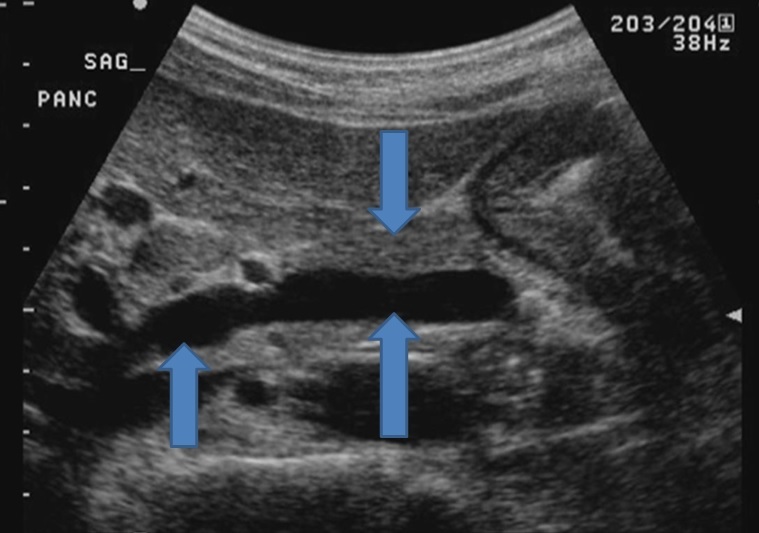

5

From top down what is the structures?

A

This image is the pancreas is sag view

1. Pancreatic neck

2. SMV

3. Main portal vein it is heading into the liver